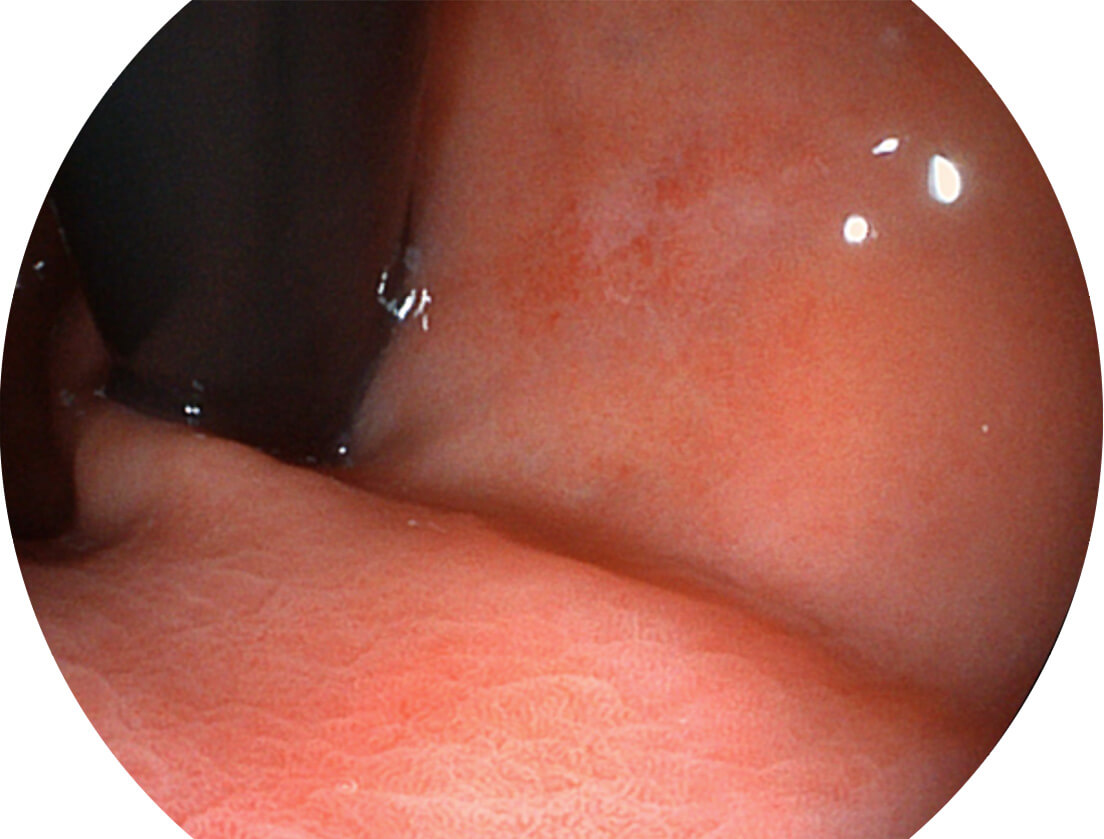

图像具有高亮度、高黏膜血管颜色对比度的特点,且不改变粘液、食物残渣、粪便的基本颜色,可在中远景下进行观察,助力消化道早期疾病的诊断。

SFI图像

采用光路合束技术,光谱自由度高,实现了更丰富的照明模式,染色模式SFI及VIST,从远景到近景,助力消化道早期疾病诊断。